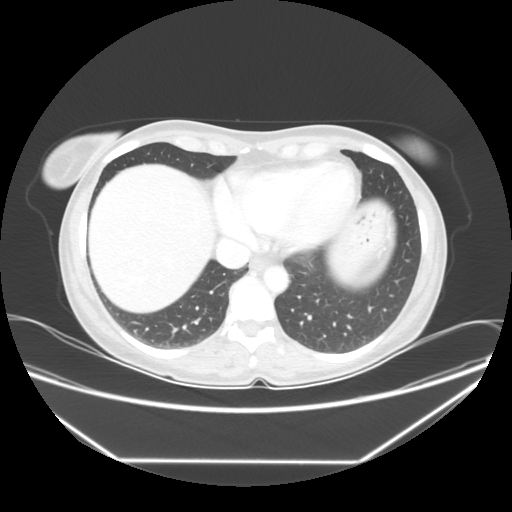

Original VENOUS CT scan

Full window (WL 1023.5, WW 4095 β†’ Low βˆ’1024, High +3071)

Lung window (WL -600, WW 1500 β†’ Low βˆ’1350, High +150)

Mediastinum window (WL 40, WW 400 β†’ Low βˆ’160, High +240)